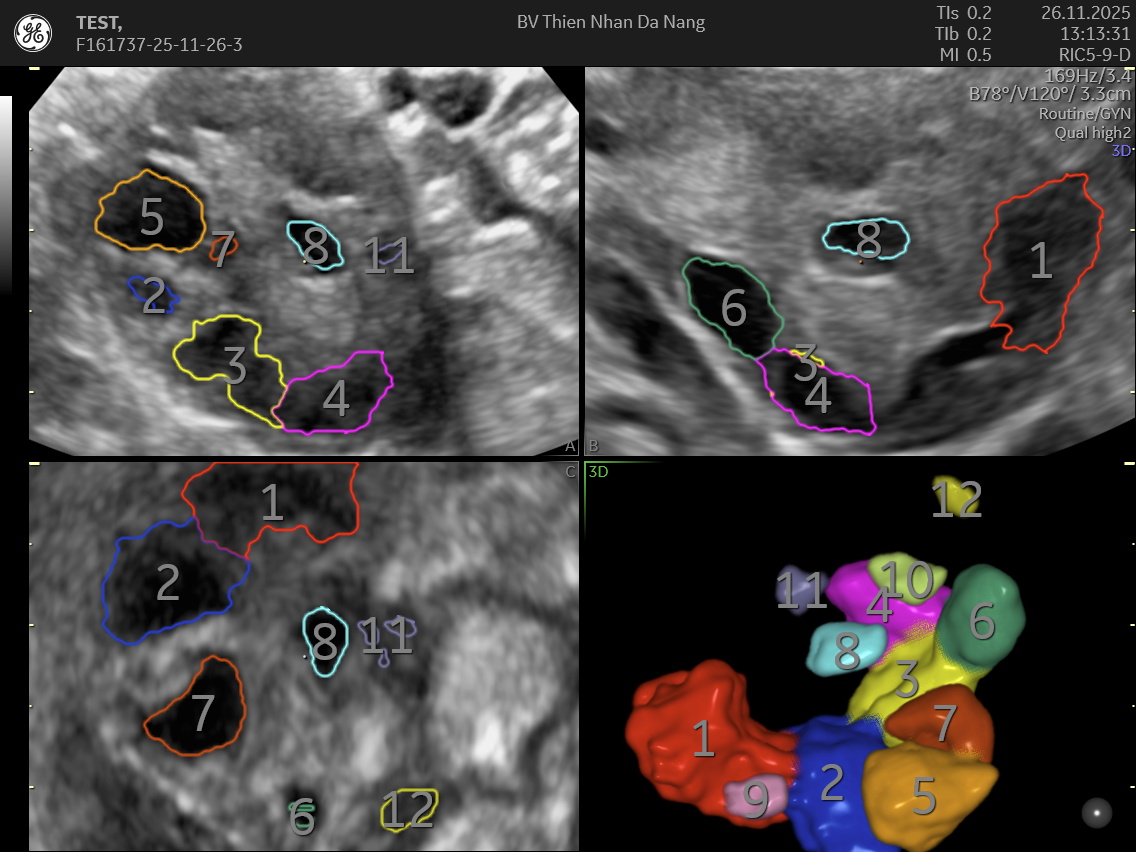

SIÊU ÂM 4D ĐẾM NANG BUỒNG TRỨNG: CÔNG NGHỆ GIÚP ĐÁNH GIÁ NANG (AFC) BUỒNG TRỨNG HIỆU QUẢ

Siêu âm 4D đếm nang buồng trứng là phương pháp hiện đại trong phụ khoa, giúp quan sát chi tiết cấu trúc buồng trứng từ nhiều góc độ và theo thời gian thực. Nhờ khả năng tái tạo hình ảnh sống động và chính xác, kỹ thuật này hỗ trợ đánh giá số lượng và kích thước nang buồng trứng, từ đó cung cấp dữ liệu quan trọng để đánh giá dự trữ buồng trứng, hỗ trợ thụ thai và điều trị hiếm muộn. So với siêu âm 2D truyền thống, siêu âm 4D giảm sai số, quan sát toàn bộ buồng trứng trong một lần quét và phân biệt nang trứng (AFC) và ảnh giả hiệu quả hơn.

Siêu âm 4D hỗ trợ đếm nang buồng trứng là phiên bản nâng cao của siêu âm 2D- 3D, cung cấp hình ảnh 3 chiều động theo thời gian thực. Khi ứng dụng trong phụ khoa, kỹ thuật này cung cấp hình ảnh buồng trứng rõ nét đến từng chi tiết, hỗ trợ bác sĩ:

Nhờ hình ảnh trực quan, siêu âm 4D giúp giảm thiểu sai số trong việc đếm nang – một trong những yếu tố quan trọng để đánh giá dự trữ buồng trứng và khả năng sinh sản của phụ nữ.

Khác với siêu âm 2D, siêu âm 4D mang lại hình ảnh chi tiết, sống động và cho phép bác sĩ xoay, phóng to hoặc thu nhỏ vùng buồng trứng. Phương pháp này giúp nhận diện chính xác từng nang, cấu trúc bên trong và mức độ tưới máu. Đây cũng là công cụ quan trọng để phát hiện u nang buồng trứng, nang lạc nội mạc.

Siêu âm 4D trong phụ khoa tại Thiện Nhân

Tại Thiện Nhân, kỹ thuật siêu âm 4D đếm nang buồng trứng được thực hiện bằng hệ thống Voluson Expert 22 (GE Healthcare – Mỹ), mang đến hình ảnh buồng trứng sắc nét với độ phân giải cao. Công nghệ UltraHD, HDlive và đầu dò âm đạo 3D giúp bác sĩ quan sát rõ từng nang, đánh giá chính xác số lượng, kích thước và cấu trúc nang noãn. Nhờ khả năng tái tạo hình ảnh chi tiết và ổn định ngay cả ở khách hàng khó siêu âm, siêu âm 4D trở thành phương pháp tối ưu để theo dõi dự trữ buồng trứng, hỗ trợ điều trị hiếm muộn và phát hiện sớm các bất thường buồng trứng.